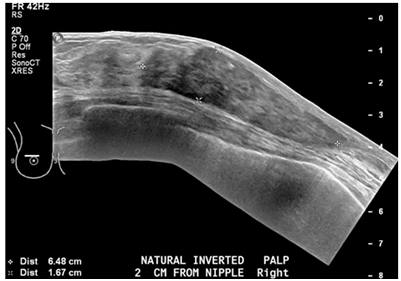

A 68year old woman was found to have an abnormal finding on routine mammography Patient has past history of type 1DM, peripheral neuropathy, hypothyroidism, HTN and a surgical biopsy left breast greater than 20years ago; with a family history of breast cancer in paternal aunt. Screening mammogram showed an apparent increased large lobular nodular density in the subareolar region deep to the nipple measuring atleast 2.5cm in the left breast. Subsequent Ultra Sound [US] of left breast showed a mass in the region of the scar site, 2cm from the nipple, measuring 41x13x46mm demonstrating some internal blood flow on Doppler. The mass was hypoechoic and slightly heterogenous with relatively circumscribed margins. Left axilla showed normal Lymph nodes [LN]. Patient underwent US-guided biopsy. Pathology showed hyalinized stromal fibrosis and chronic mastitis. This benign pathology was discordant with mammographic and sonographic imaging findings. Therefore, surgical excision was recommended with a breast surgeon follow up. Soon thereafter, patient presented with a painless palpable area of concern in the superior and subareolar Right breast of two weeks duration. Mammography and US of right breasts showed a very dense tissue in the palpable area of concern, corresponding to heterogeneous, slightly hypoechoic mass with relatively circumscribed margins measuring 38x18x65mm with internal vascularity. It had a very similar appearance to the area that was biopsied on the left breast in a similar position which demonstrated stromal fibrosis and chronic mastitis. A coarsely calcified vessel was noted running through the area of concern. No abnormal lymph nodes were detected. Given the bilaterality and history of diabetes, a preliminary diagnosis of bilateral diabetic mastopathy was made. A decision was made to follow up annually with regular mammography. In September 2017, patient developed retraction in the skin and nipple areolar complex in both breasts. Mammogram and US of both breasts revealed large densities which were relatively stable, however the skin changes prompted repeat biopsies. Thickened tissue on both breasts was excised and sent for pathology. Pathology showed collagenous stroma with keloidal features and an increased concentration of stromal spindle cells. The breast lobules revealed atrophy, infiltrated by mature small lymphocytes. A perivascular lymphocytic infiltrate was noted. The morphological features were consistent with diabetic mastopathy. The rest of the breast tissue revealed apocrine metaplasia and ductal dilatation. No atypia or malignancy was identified.

Diabetic mastopathy, also known as lymphocytic mastitis or lymphocytic mastopathy is seen occasionally in premenopausal women who have longstanding type 1 diabetes mellitus. This case underlines the importance of considering diabetic mastopathy on the list of differential diagnoses when evaluating breast lesions in a diabetic woman. Patients with DMP clinically present with painless, irregular hard unilateral or bilateral breast masses. It is rare as it represents represent 0.6% to 13% of benign lesions observed in woman with type 1 diabetes.2 Core biopsy is recommended for diagnostic confirmation. Pathology shows dense keloid-like fibrosis and periductal, lobular, or perivascular lymphocytic infiltration.3−5 The pathogenesis is not fully understood but many theories involving the effects of sustained hyperglycemia and glycosylated end products on the connective tissues of the breast have been proposed. Also it may represent an autoimmune reaction as the histologic features are similar to those seen in other autoimmune diseases.6 There are no large series with long-term follow up, but most reports recommend annual clinical and radiological monitoring and, in case of a new lesion, an additional biopsy must be considered. Once the diagnosis is established, excision is not necessary and malignant transformation has not been described. Conservative management is adequate for the majority of patients. Lesions have a tendency to recur after resection.2,7 Recognizing the presentation of this rare condition can help avoiding unnecessary surgical intervention (Figures 1 & 2).

Figure 1 Ultrasound of the breast showing Mastopathy changes, 311x222mm (72x72 DPI).